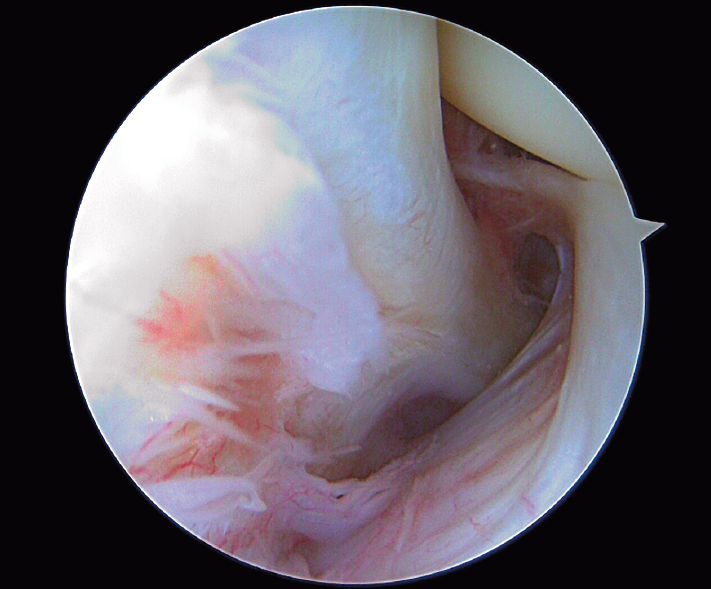

Imagen artroscópica de la parte más posterior del compartimento externo de la rodilla donde se observa el tendón poplíteo dentro del hiato poplíteo. Imagen obtenida desde un portal anterolateral proximal (aproximadamente 0,5 cm lateral y distal a la porción más lateral del polo superior de la rótula).